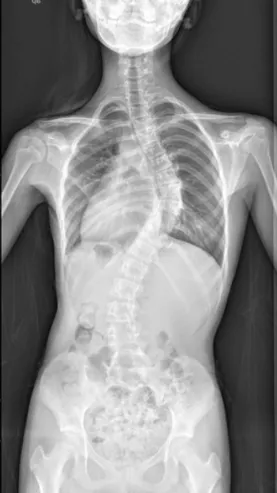

特发性脊柱侧凸是所有脊柱侧凸中最多见的,原因不明。其中青少年特发性脊柱侧凸(AIS)最常见,发病率1.5%-3%,占全部脊柱侧凸的75%-80%。约80%的AIS患者需佩戴支具以控制侧凸进展,佩戴支具的患者中,约1/4最终需要手术治疗。

▲ 女,14岁,青少年特发性脊柱侧凸